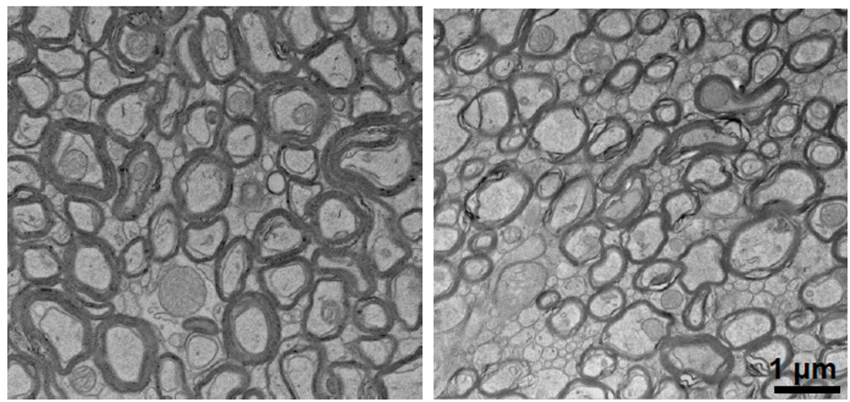

Electron microscopy showing myelin differences with lithium deficiency

Lithium deficiency thinned the myelin that coats neurons (right) compared to normal mice (left). Electron microscopy revealed this structural change helps explain why lithium levels matter for brain function.

Thick myelin coating protects neurons, preserves synaptic connections and axons

Lithium Deficient

Thinned myelin, loss of synapses and axons, impaired neuron-protecting structures